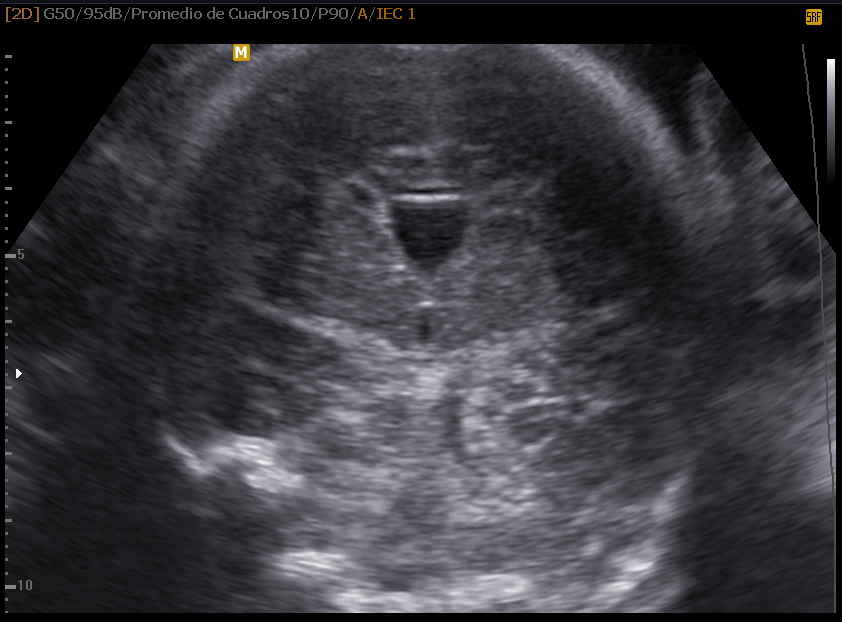

Columna vertebral

La columna vertebral, el eje neurológico que articula las funciones motrices y autonómicas del cuerpo comandadas por el cerebro y los sistemas vegetativos, es una estructura lineal mas sencilla de evaluar pero no menos importante desde el punto de vista diagnóstico por ser el asiento de las malformaciones más comunes del sistema, la espina bífida.